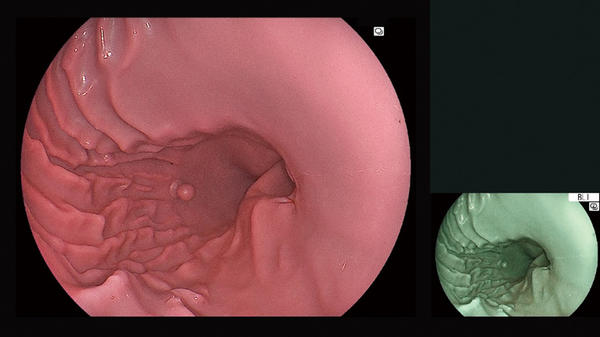

(4)白色光画像と画像強調機能の画像を同時に表示するマルチオブザベーションモードを搭載

白色光画像と画像強調機能の画像を同時に取得し,観察モニター上に表示するマルチオブザベーションモードを搭載した。これにより,画像強調機能のON/OFFを切り替える手間を削減し,スムーズな観察をサポートする。

マルチオブザベーションモードの画面

白色光画像と画像強調機能の画像を同時に取得して観察モニター上に表示し,スムーズな観察をサポートする。